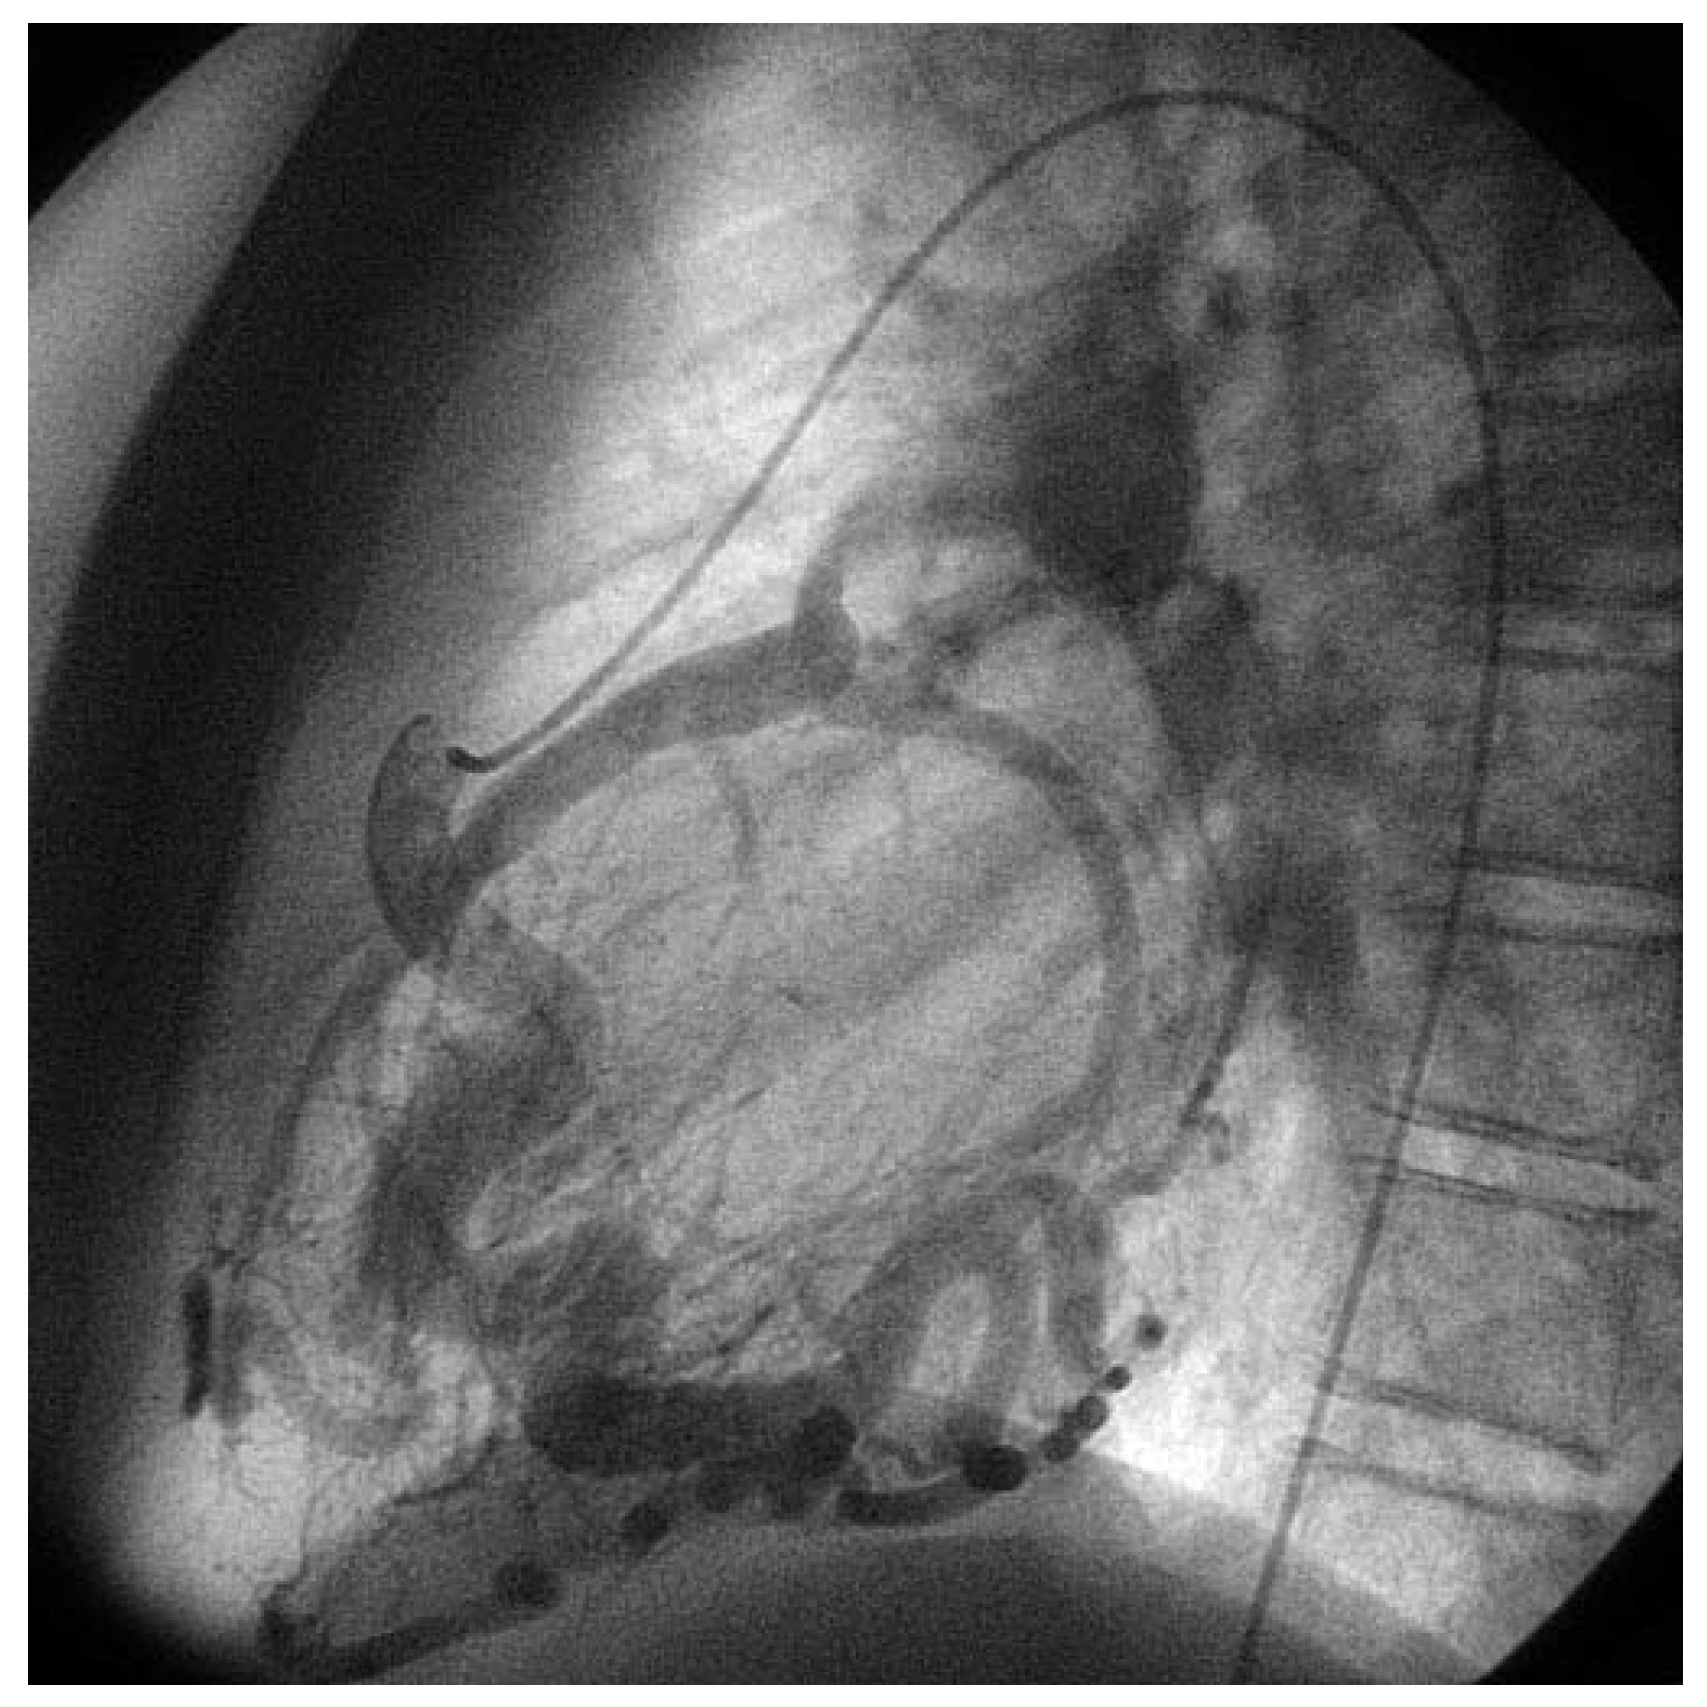

Asymptomatic Bland-White-Garland Syndrome in a 13-Year-Old Girl

Case report